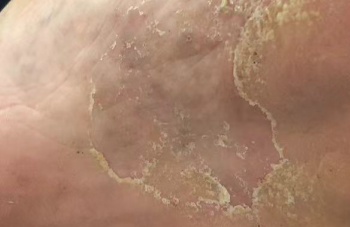

脚痒、脱皮、起水泡?小心这种“会传染”的麻烦找上门